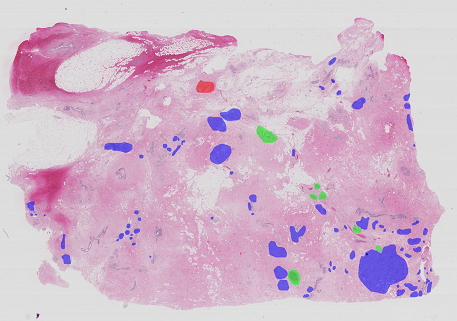

2.2.2 Whole-slide images dataset

Whole-slide images (WSI) are high resolution images containing the entire sampled tissue. Because of that, each WSI can have multiple pathological regions. The BACH’s Part B dataset is composed of 30 WSI for training and 10 WSI for algorithm testing. Specifically for training, the organization provided 10 pixel-wise annotated regions for the Benign, In situ carcinoma and Invasive carcinoma classes and 20 potentially pathological WSIs that were not annotated by the experts. The provided annotations aim at identifying regions of interest for the diagnosis on the lowest magnification setting and thus may include non-tissue and normal tissue regions, as depicted in Fig. 3. The distribution of the labels is shown in Table 1.

The WSI images were acquired in 2013–2015 from patients from the Castelo Branco region (Portugal) with a Leica SCN400 (from Centro Hospitalar Cova da Beira), and were made available on .svs format, with a pixel scale of 0.467 μ𝜇\mum/pixel and variable size with width \in [39980 62952] and height \in [27972 44889] (pixels). The ground-truth was released as the coordinates of the points that enclose each labeled region via a .xml file.

Refer to caption

Fig. 3: Example of a pixel-wise annotated whole-slide image from the training set . \blacksquare benign; \blacksquarein situ; \blacksquare invasive.